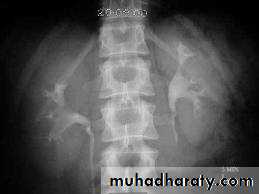

A. First a plain x-ray of the abdomen is taken before the injection of the contrast media, also known as A KUB (kidney, Ureter and Bladder). Calcification & stones may be obscured & missed by contrast media if plain film not takenfirst .B. Films taken after injection of contrast’ medium:

1. Nephrogram phase (Immediately after injection of contrast) .